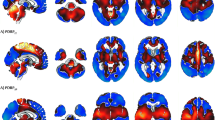

Individual brain PET study was quantified and compared to an age-matched normal database using NeuroGam Software (GE Medical Systems; Segami Corporation, Columbia, MD, USA). This software applies an affine anatomical coregistration by blocks of data defined in the Talairach space. An anatomical standardization and a voxel value normalization to the cerebral maximum value was done. Patient and subjects control database comparison was done voxel by voxel in the brain cortex and the basal ganglia creating a Z-score map [12].

The Z-score maps were displayed either in the standard cuts or by overlay on a 3-D anatomical topographic representation by means of a specific colour scale. For NeuroGam analysis, the reference population contained: 28 controls for 50–60 year-old patients (sex ratio men/women = 1.54), 30 controls for 60–70 year-old patients (sex ratio 1.72), 31 controls for 70–80 year-old patients (sex ratio 1.21), and six controls for 80–90 year-old patients (sex ratio 2). For individual patient analysis using NeuroGam software, we studied semi-quantitatively intra- and inter-individual differences in metabolism in the cerebral and cerebellar cortex using 3-D reconstruction FDG-PET images (considering the four different cerebral lobes, i.e. the frontal, the parietal, the occipital, and the temporal lobes; and each cerebellar hemisphere), and the basal ganglia using axial views (considering the caudate nucleus, the lentiform nucleus, and the thalamus). A cerebral cortical lobe, a cerebellar cortical hemisphere, or a basal ganglia substructure was considered hypometabolic when a clear zone of hypometabolism of more than 2 standard deviations (SD) was found. For each cerebral cortical lobe, hypometabolism was called slight when <50 % of the surface of the involved lobe showed a hypometabolism of more than 2 SD, and called severe when more than 50 % of the surface showed hypometabolism of more than 2 SD. Lobes showing hypometabolism less severe than 2 SD were called ‘normal’. To study lateralization of the cerebral lobe involvement in a given patient, hypometabolism in the concerned lobe was considered lateralized when one side was hypometabolic and the other side normal (i.e. no areas with hypometabolism of >2 SD), or when the involved (>2 SD) area exceeded by 30 % or more the involved (>2 SD) area in the contralateral lobe. In cases where bilateral extensive lobe hypometabolism was present with the least involved lobe showing >2 SD hypometabolism in more than 70 % of its lobe surface, lateralization was considered present when one lobe showed more than 30 % of lobe surface with >3 SD hypometabolism when compared with the opposite side.

FDG-PET individual patient analysis using NeuroGam

Semi-quantitative data of cerebral cortical and basal ganglia FDG-PET metabolism are shown in Tables 2 and 3. When considering the cortex of the four different lobes in each hemisphere in each patient, 49 out of 72 lobes (68 %) were hypometabolic (including 28 lobes with slight and 21 lobes with severe involvement) on FDG-PET, leaving one frontal, four temporal, four parietal, and 14 occipital lobes with normal metabolism. Lateralization was seen in 29 of the 36 lobes (81 %). The remaining seven lobes without lateralization did not show hypometabolism. Thus, when present, cortical lobe hypometabolism was never symmetrical.

The shared FDG-PET pattern of hypometabolic cortical zones in all patients was asymmetrical hypometabolism in the medial parietal lobe, the lateral and medial frontal lobe (typically sparing the Brodmann’s area 4 and 6, and the anterior cingulate cortex), and to a lesser degree the lateral parietal lobe. Associated variable temporal lobe hypometabolism was also seen. Hypometabolism in the lateral parietal lobe was less severe or involved smaller areas than in the medial parietal lobe and the frontal lobe except in one patient (patient 3, showing profound lateral parietal hypometabolism). Associated temporal hypometabolism was less severe than in the medial parietal and the frontal lobe in five patients, equally severe in three, and more severe in one patient (patient 3).

FDG-PET metabolism in the basal ganglia was significantly decreased in 12 (with 11 with slight and one with severe involvement) out of 54 (22 %) basal ganglia structures (i.e. considering caudate nucleus, lentiform nucleus, and thalamus of each hemisphere in each patient), corresponding to 6 patients showing basal ganglia hypometabolism (all lateralizing to the side of the predominant cortical hypometabolism) with the caudate nucleus as the most frequently involved hypometabolic basal ganglia substructure. When basal ganglia substructure hypometabolism was present, lateralization was found in all.